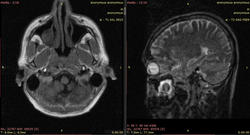

Видны изменения в стволе мозга (мост), белом веществе мозжечка и, помимо этого, белом веществе большого мозга (виден по крайней мере один перивентрикулярный очаг в левой теменной доле, нельзя исключить более мелких очагов - трудно судить по низкопольным картинкам).

Такая картина характерна для центрального понтинного миелинолиза. Он возникает в основном у алкоголиков на фоне острый осмотических нарушений. При этом поражается в основном мост, но также могут быть видны очаги в других отделах мозга (экстрапонтинный миелинолиз). Поэтому и понтинные, и экстрапонтинные изменения объединяются термином "синдром осмотической демиелинизации". Вот здесь разные случаи: http://radiopaedia.org/articles/central-pontine-myelinolysis

В пазухе - да, скорее всего мицетома, но вряд ли это как-то связано с мозгом)))

C учетом наличия очагов в мозжечке и перивентрикулярно - скорее РС.

Наверное, вы правы. В продолговатом мозге тоже очаги.